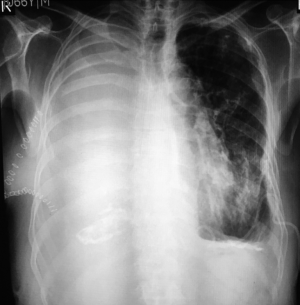

The empty space resulting from removal of the lung is usually filled up with serous fluid (Figure 2). In case of no postoperative complication, 70% of the chest cavity is filled within a mean of 3 days (22). Median time to complete opacification of the chest with fluid was slightly over two months. It has also been reported that a spontaneous emptying of pleural fluid from the pneumonectomy cavity can occur without any evidence of a bronchopleural fistula (23). This was thought to be the results postoperative intrapleural pressure shifts.